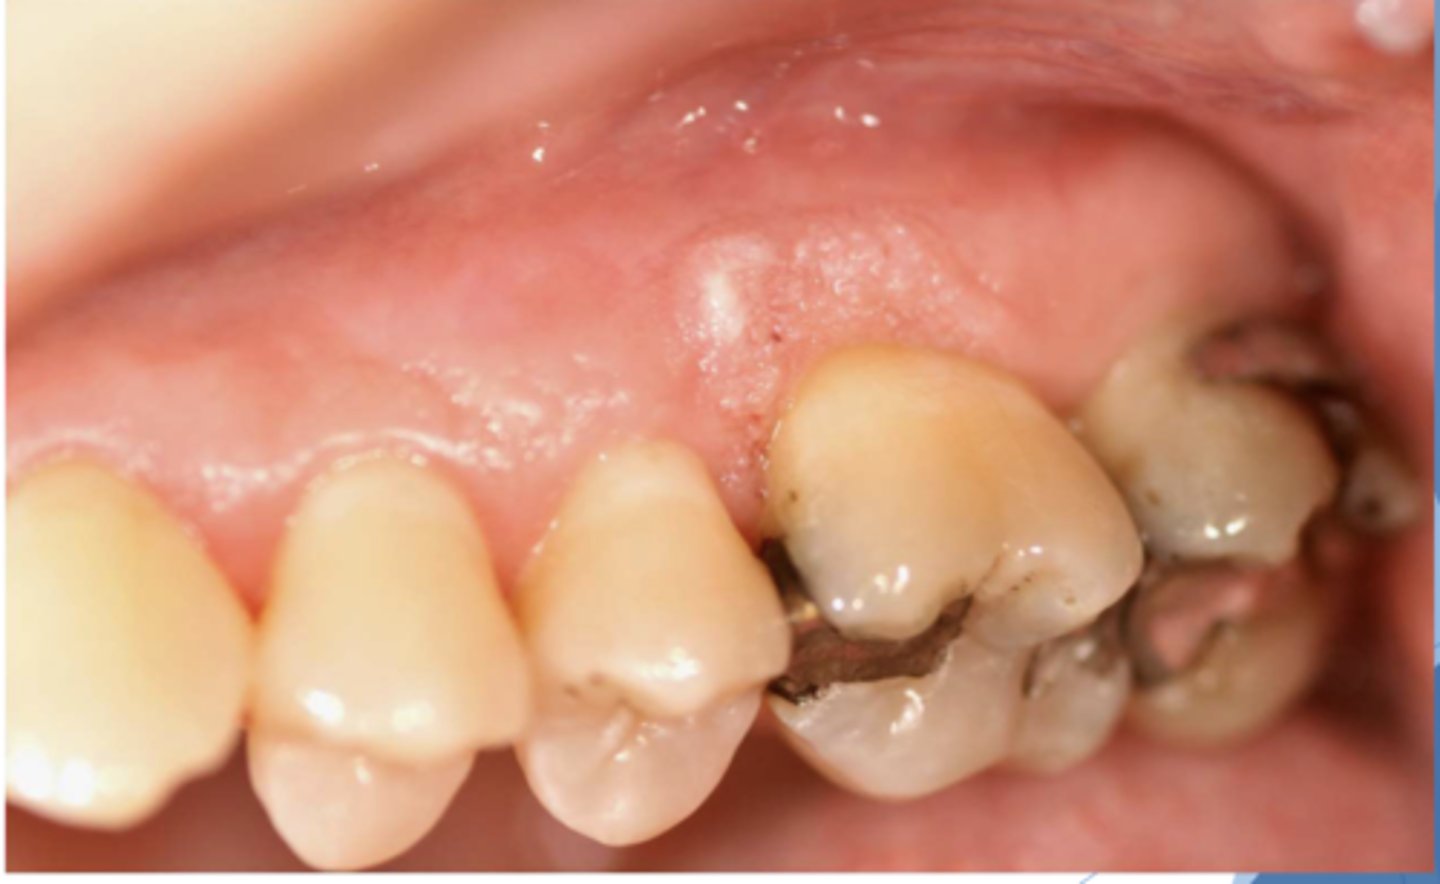

Find the lesion. What diagnosis differential would you consider?

well-demarcated papillary lesion on the buccal dental papillae between #20 & #21; Possible Differential:

-HPV --> papillary, will need to confirm with biopsy, HPV testing

-squamous cell carcinoma

-verruciform xanthoma --> benign lesion that may resemble squamous papillomas or squamous cell carcinoma

*v. xanthoma is what this lesion is but there's no way to differentiate from the differential clinically w/o HPV testing/biopsy